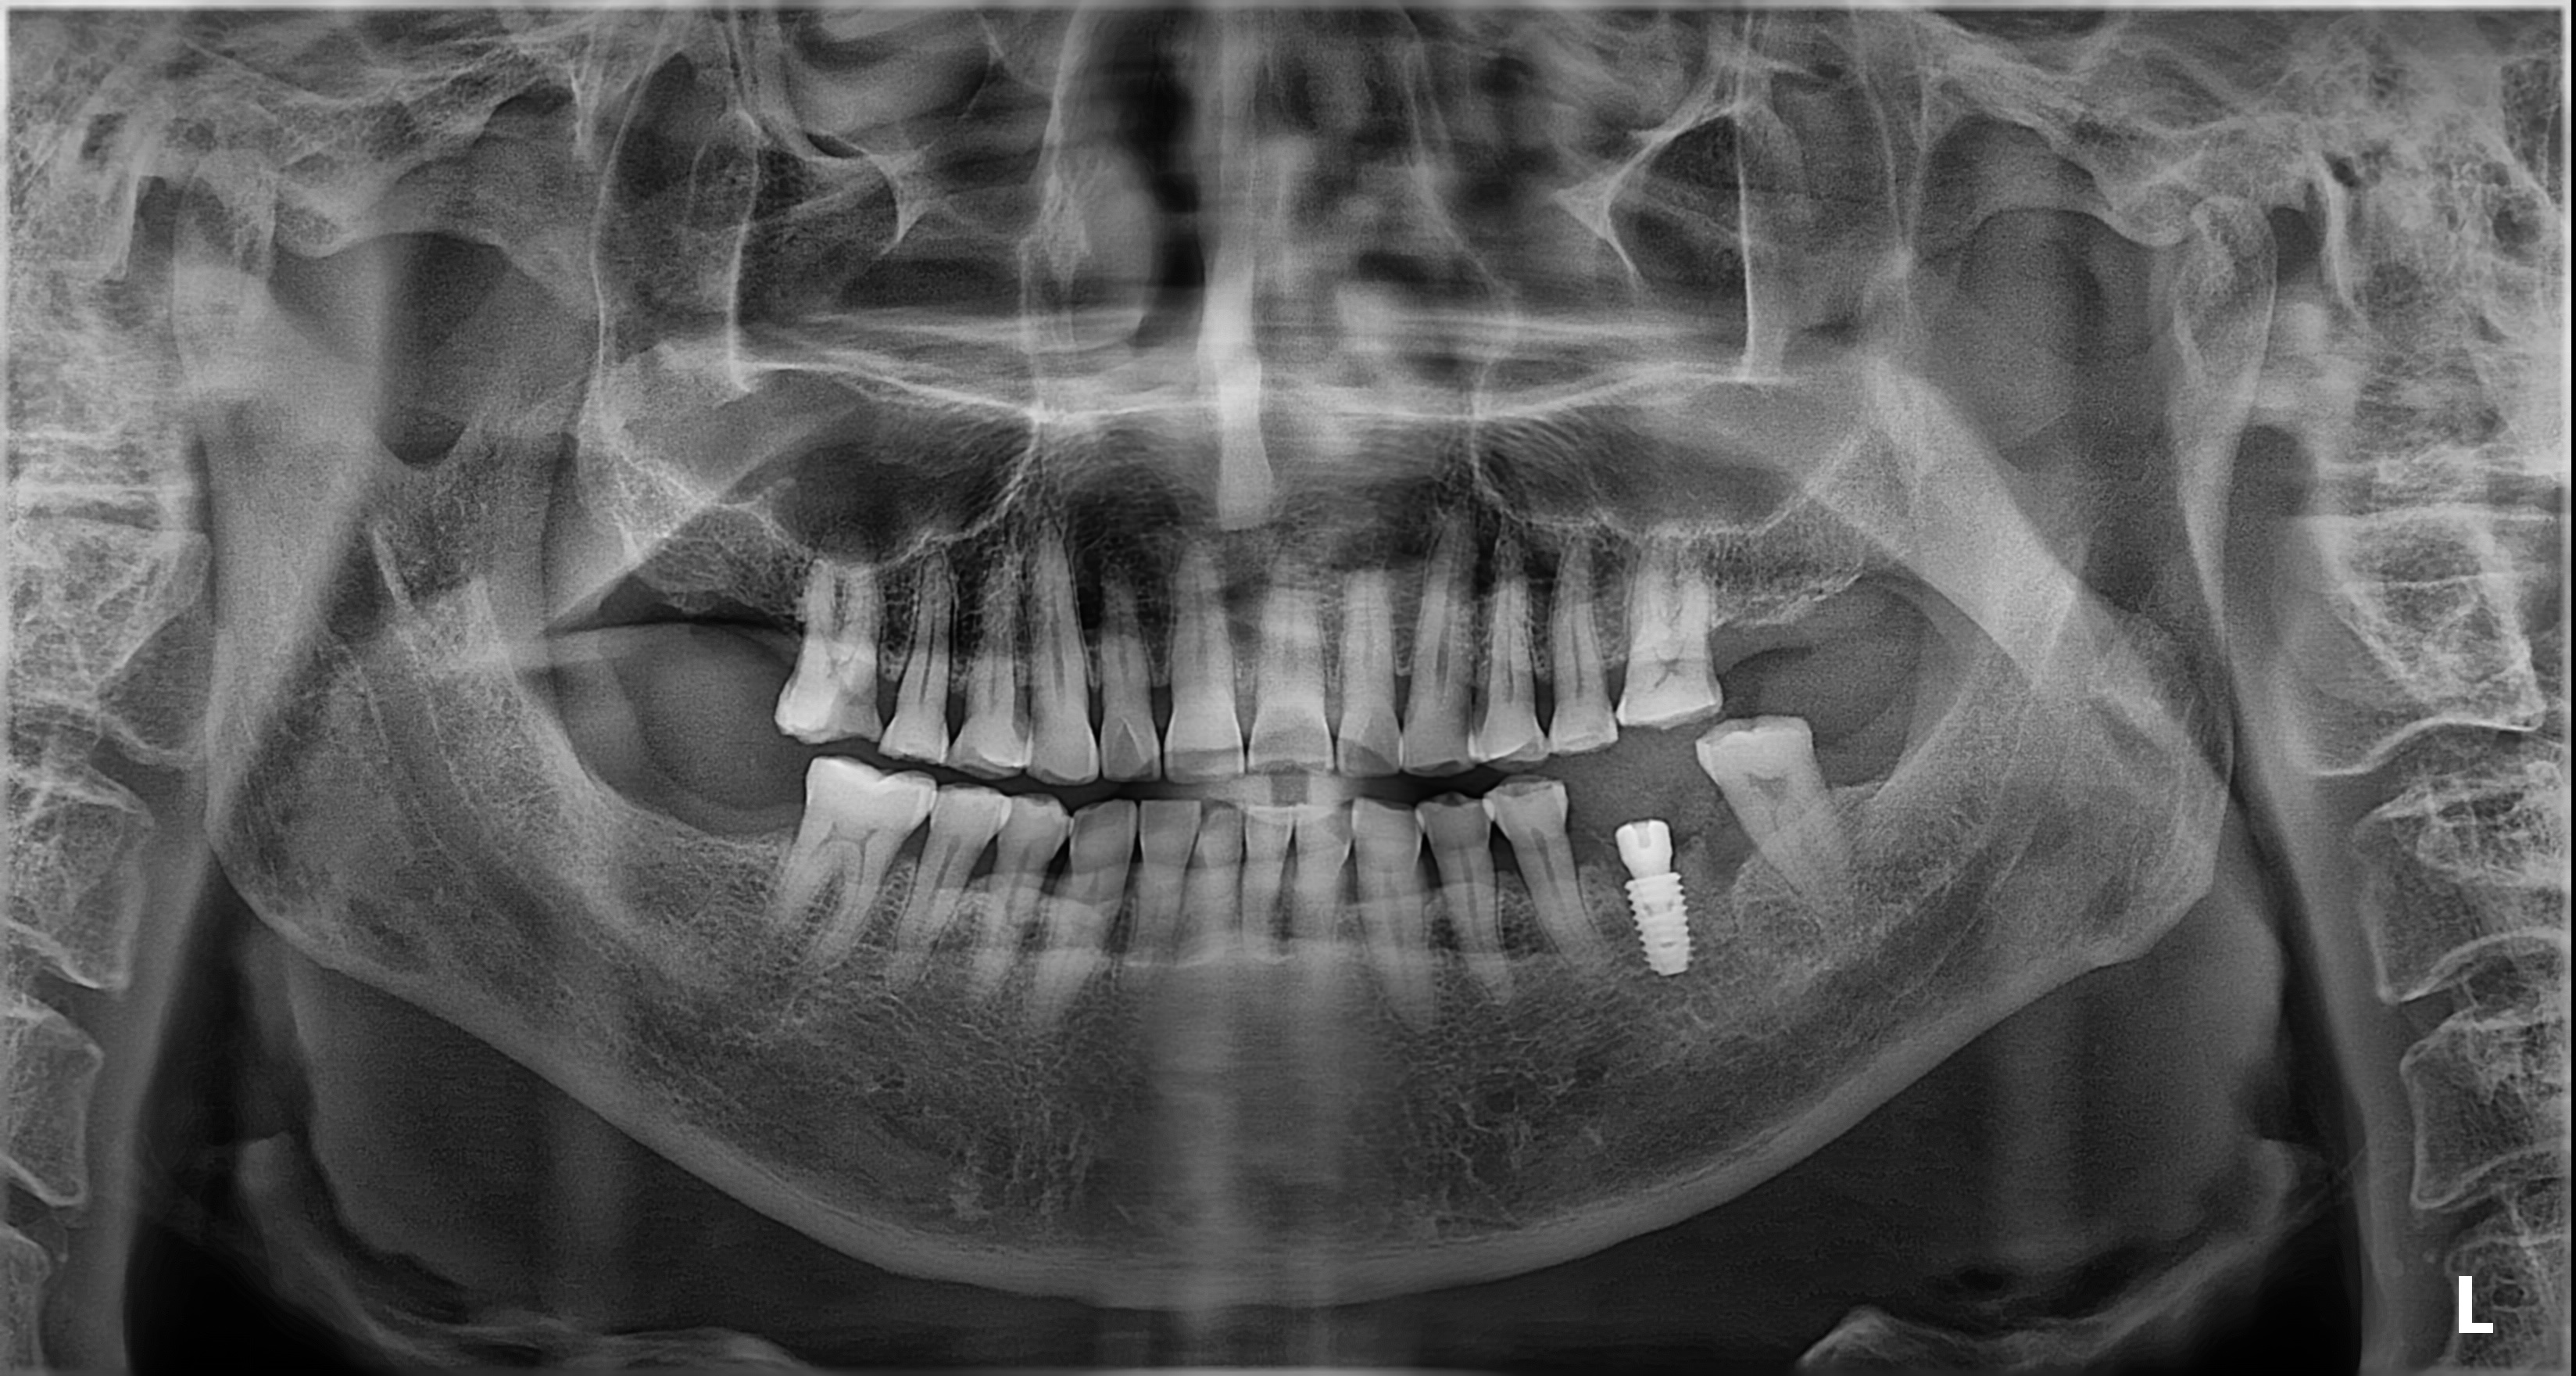

임플란트 시술 사진

임플란트의 5년 성공율은

최근 발표된 논문들까지 종합해도

90~95% 이상으로 발표되고 있습니다.

매우 높은 성공율입니다.

하지만, 실패한 임플란트를 같은 자리에

재식립했을 때의 성공률은 70%대로 떨어집니다.

(J Oral Maxillofac Surg 78:375-385, 2020)

초기에 발견하고 재식립했을 때는 성공율이 높아집니다.